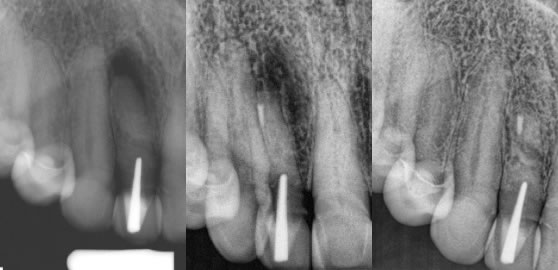

6. Various Unique cases that I simply categorize as something different. (figures 19,20,21) and (figures 22,23,24)

Figures 19,20,21: pre-op / post-op / 5 month recall

Significant root-end resorption. I did see the original RCT performed by a previous endodontist and the gutta percha was exactly to the root end, thus the resorption has occurred after the RCT was completed. The coronal restorations were great and so I performed apicoectomy in this case. The healing was nearly complete at just 5 months.

Figures 22,23,24: pre-op / post-op / 6 month recall

My patient told me she had 3 RCT’s on each tooth and 2 sets of crowns over the past 20 years on the teeth. I had actually recommended retreatment again because the RCT’s were inadequate, but she was not at all interested in anything other than the least amount of hassle and treatment since she had been through so much already. I performed the apicoectomy on both teeth and she reported her teeth have never felt this good in 20 years.

7. Previous Apicoectomy treatments that have had an infection recurrence. (figures 25,26,27)

Figures 25,26,27: pre-op / post-op / 14 month recall

This patient came to me understanding from her referring dentist that there is likely not much to be done and the bridge will be lost. Retreatment endodontics is not indicated and we decided to do what we can to save this bridge vs. bridge removal, extraction, implant, possible sinus lift, etc. The apicoectomy approach is far less involved and resulted in saving this bridge.